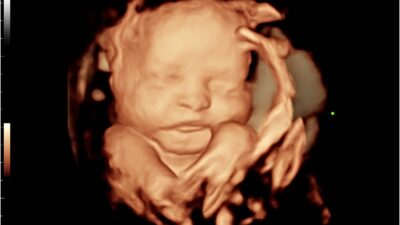

Now, enter the 3D ultrasound! This amazing technology takes countless slices and stacks them together using a computer, creating a stunning three-dimensional image of the entire loaf. Suddenly, you can see the shape, contours, and surface details in all their glory!

A 3D ultrasound is a special kind of scan that gives you a three-dimensional view of your baby (or another organ), making it look more like a photograph than a flat, shadowy image.

You’ll be able to see your baby’s face, hands, feet, and overall shape in incredible detail, allowing you to appreciate all those adorable surface features.

So, how does it work? The ultrasound machine captures thousands of images from different angles and then magically blends them into one cohesive 3D picture!

With a regular (2D) ultrasound, you’re looking at a flat, black-and-white cross-section. But with a 3D ultrasound, you get a golden-toned, three-dimensional image that brings your baby to life!

Regular ultrasounds are fantastic for medical checks—measuring bones, assessing organs, and ensuring your little one is developing properly. They’re the go-to tool for diagnosis! On the flip side, 3D ultrasounds shine when it comes to seeing those precious features—like your baby’s face, lips, fingers, and toes. They can even help spot surface issues like a cleft lip.

A regular ultrasound looks like a collection of shadows and shapes (which experts can read like a book). In contrast, a 3D ultrasound resembles a detailed, sculpted model of your baby, showcasing all those adorable details!